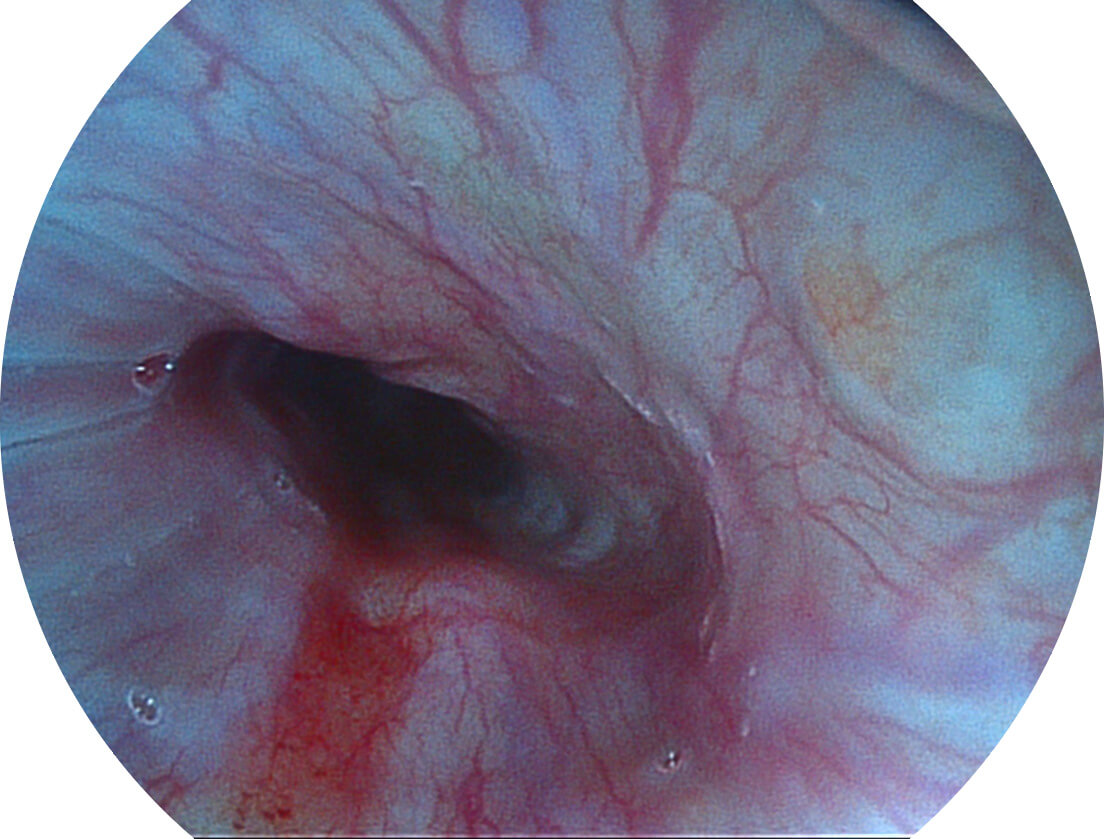

強(qiáng)調(diào)淺層黏膜結(jié)構(gòu)的同時(shí),保證照明亮度和提升淺層微血管與中層血管顏色對比度,病變邊界更清晰。

• 白光圖像 VIST圖像